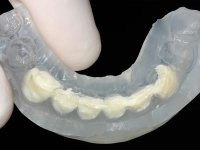

Realizado o diagnóstico e tomada a decisão quanto ao tratamento a executar, tornou-se importante definir qual a sequência de trabalho a adotar no sentido de conseguir a reabilitação da D.V.O. (V.D.O), de forma progressiva e equilibrada. Na primeira fase fez-se uma pré-impressão da arcada inferior com silicone tipo “putty” e em seguida realizou-se o preparo dentário de todo o sector posterior. O preparo para os overlays foi feito coronalmente à linha amelo cementaria no sentido de ser o mais conservador possível. A impressão foi feita com técnica de dupla mistura após afastamento gengival realizado com pasta de caulino. A provisória foi realizada com resina composta de polimerização dual. Em laboratório foram realizados os overlays após se ter aberto ligeiramente (1,5mm) a D.V.O. nos modelos montados em articulador semi-ajustável. Simultaneamente o sector antero-inferior foi encerado no sentido de acompanhar este aumento da D.V.O. Também foi confecionada uma chave de silicone translucido para posterior confeção dos provisórios antero-inferiores. Em boca foi primeiro realizada a provisionalização dos dentes anteriores utilizando resina composta previamente aquecida após preparação das superfícies dentárias para a adesão. Foi colocado o dique de borracha para promover o isolamento absoluto e posteriormente foram colados os overlays. Em laboratório foi realizada nova chave de silicone para confecionar os provisórios antero-superiores. Seguidamente em boca foram preparados os seis dentes antero-superiores após colocação do fio de afastamento gengival. Feita a preparação adequada das superfícies dentárias foi realizada a impressão com técnica de dupla mistura e a respetiva provisória. Em laboratório foram confecionadas 6 facetas feldespáticas num modelo de trabalho tipo “Geller”. A provisória foi removida e as facetas foram coladas em boca utilizando um isolamento relativo competente. Esta opção foi tomada em virtude de uma prévia experiencia negativa com a colocação do dique de borracha na mandibula. Após a colagem dos laminados antero-superiores foram dadas 12 semanas para avaliar a adaptação do paciente à nova situação e então iniciar a confeção das facetas antero-inferiores. Após colocação do fio de afastamento gengival. foram feitos os preparos dentários adequados e em seguida foi feita a impressão. Também foi feita a preparação do dente 3.4 que, entretanto, tinha sofrido uma fratura do overlay. As facetas e a restauração do 3.4 foram realizadas num modelo de trabalho tipo “Geller”. Após remoção da provisória, as facetas foram coladas em boca, utilizando um isolamento relativo pelas razões apontadas anteriormente. Após colocação do trabalho o paciente foi reabilitado por outros colegas com um implante na zona do 2.6 e substituição da coroa aparafusada sobre o implante colocado no local do 3.5. Posteriormente surgiram fraturas nos overlays dos dentes 4.7 e 3.7 que foram reabilitados com overlays em Zr.